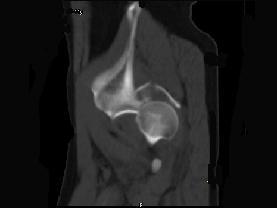

问题 男,44岁,有外伤史,请结合所提供的图像,选择最佳答案 ( )

选项 A、左髂骨骨折 B、左坐骨骨折 C、左髋关节脱位 D、左髋臼骨折并左髋关节脱位 E、左髋臼骨折

答案 D